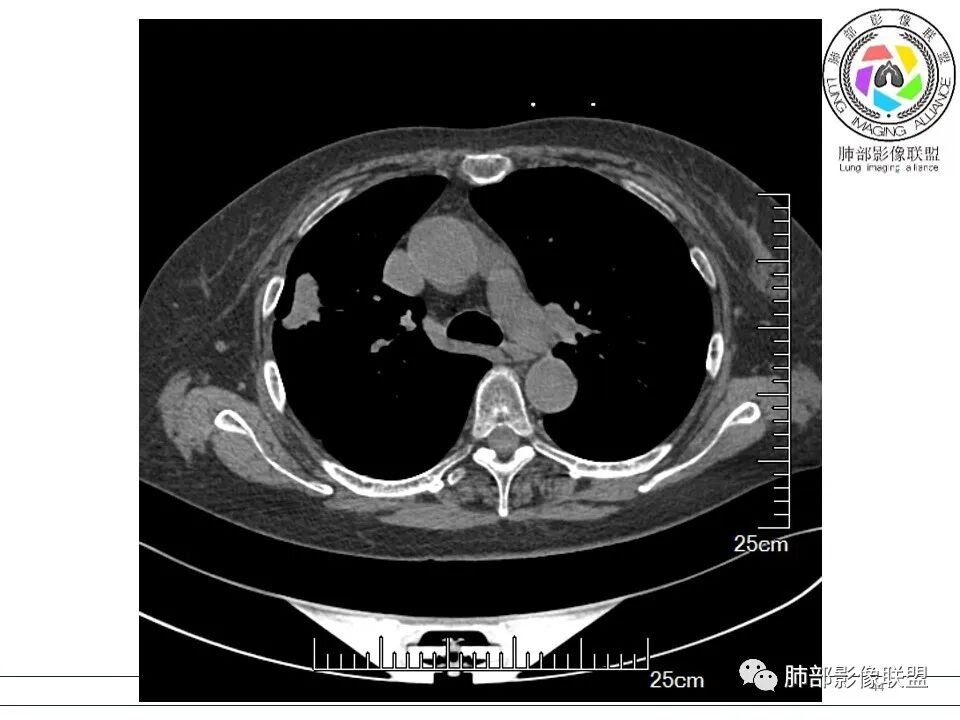

衡妈: 老年女性,右肺上叶沿胸膜下不规则实性病灶,长轴平行于胸膜,有结节融合感,边缘部分彭隆部分平直,周围可见数条纤维灶影,病灶内可见充气支气管征未达远端,首诊考虑慢性炎性肉芽肿,隐球菌?机化性肺炎?建议增强扫描及ct下穿刺活检。

晨读:女,70,未诉症状。风湿性多肌痛病史,口服强的松等药物治疗。胸部CT:右肺上叶多发不规则斑片影,沿支气管分布,部分病灶侧向融合、平行于胸膜,边缘平直内收为主、部分彭隆,周围模糊晕、可见数条纤维灶影,胸膜牵拉,病灶内可见充气支气管征、管腔不畅,考虑慢性炎症,PC?OP?鉴别腺Ca、SCLC等。

6、支气管和血管:支气管通畅或进入后堵塞,增强可见血管造影征或血管影消失。

7、强化:增强强化程度各异,从轻度到中度强化均可。明显/显著强化相对少见。